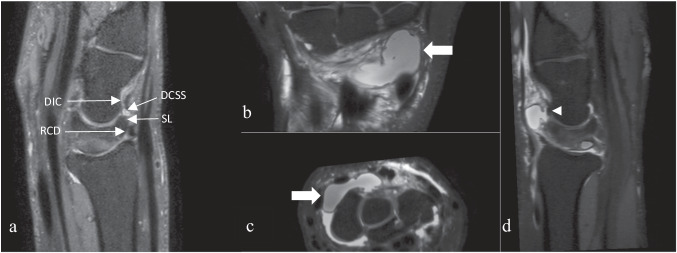

Fig. 2.

a Sagittal reconstruction of 3D DP SPAIR. DIC, dorsal intercarpal ligament; RCD, radio-carpal ligament; DCSS, dorsal capsular scapholunate septum with a ganglion inside; SL, scapholunate ligament. Images of large dorsal wrist ganglion using 3D DP SPAIR in MPR mode; b coronal plane; c axial plane; d sagittal plane. Arrow = ganglion; arrowhead = scapholunate ligament

The descriptive statistics of our study population are summarized in Table 2. Inter-observer agreement for cyst detection was almost perfect (weighted Kappa: 0.89; 95% CI: 0.84 to 0.94). Of the 295 wrists studied on imaging, 50.8% (n = 150) showed a dorsal wrist cyst centered on the DCSS and the deep part of the dorsal SL. In this population of patients with cysts, the mean age was 38.7 years (aged 15 to 75 years), and 50.6% (n = 76) of patients had an acute trauma requiring examination. The sex ratio was 0.6 with 58.7% women (88/150) and 41.3% men (62/150). 88% of patients were right-handed (n = 132) and 49.3% (n = 74) of wrists had a ganglion on the left side, showing an equitable distribution between the two sides. The median cyst volume was 8.7 mm3 and 8.2 mm3 for observers 1 and 2, respectively (minimum: 0.52 mm3; maximum 2555 mm3) with the median major axis at 3 mm ranging from 1 to 25 mm for both observers. Most cysts were small, with a 75th percentile volume and major axis of 35.5 mm3 and 6.3 mm, respectively (see Fig. 3). Volume and major axis cysts measurements displayed very high agreement between observers of 0.96 (95% confidence interval 0.95 to 0.97) and 0.91 (95% confidence interval 0.88 to 0.93), respectively. It should be noted that there are differences in measurements between observers, particularly regarding the few cases of cysts with large volumes (see Fig. 4). Only 31% of cysts (47/150) were large enough to have a direct relationship with the extrinsic ligaments, particularly the dorsal intercarpal ligament (DIC) and radiocarpal ligament (RCD) (see Fig. 2) corresponding to type 3 and 4 cysts according to the classification proposed by Guérini [8] (type 2, 3, and 4 in modified classification, see Table 2). When applying the modified classification, our inter-observer agreement was 0.76 (95% confidence interval 0.67 to 0.85). Among the small cysts isolated on DCSS (n = 103/150), the pedicle was not visible in 31 patients (modified classification 1a n = 31/150, see Table 2).